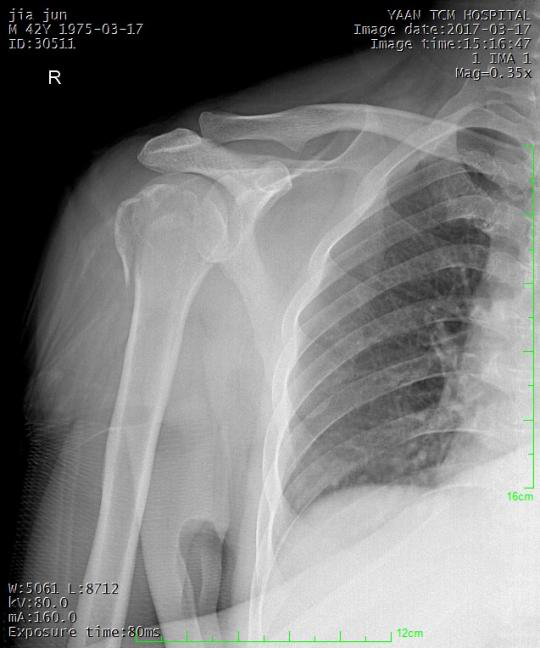

常见骨折手法整复:

桡骨下端骨折

术前:

术后